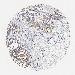

OVARIAN CANCER - Protein expressioni

A mouse-over function shows sample information and annotation data. Click on an image to view it in a full screen mode. Samples can be filtered based on level of antibody staining by selecting one or several of the following categories: high, medium, low and not detected. The assay and annotation is described here.

Note that samples used for immunohistochemistry by the Human Protein Atlas do not correspond to samples in the TCGA dataset.

Antibody stainingi

Antibody staining in the annotated cell types in the current human tissue is reported as not detected, low, medium, or high, based on conventional immunohistochemistry profiling in selected tissues. This score is based on the combination of the staining intensity and fraction of stained cells.

Each image is clickable and will lead to virtual microscopy that enables deeper exploration of all samples and also displays staining intensity scores, fraction scores and subcellular localization as well as patient and tissue information for each sample.

Antibody CAB004222

Cystadenocarcinoma, serous, NOS

Cystadenocarcinoma, mucinous, NOS

Carcinoma, endometroid

Carcinoma, NOS